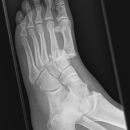

Fuß

Lisfranc Luxationsfraktur